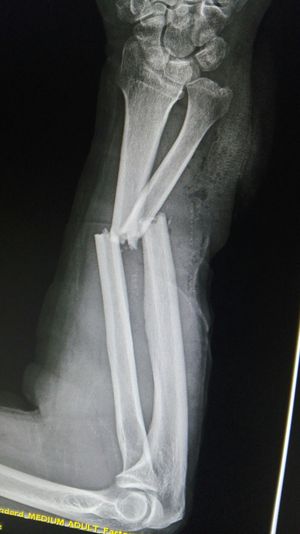

Xray

Fractures

Forearm